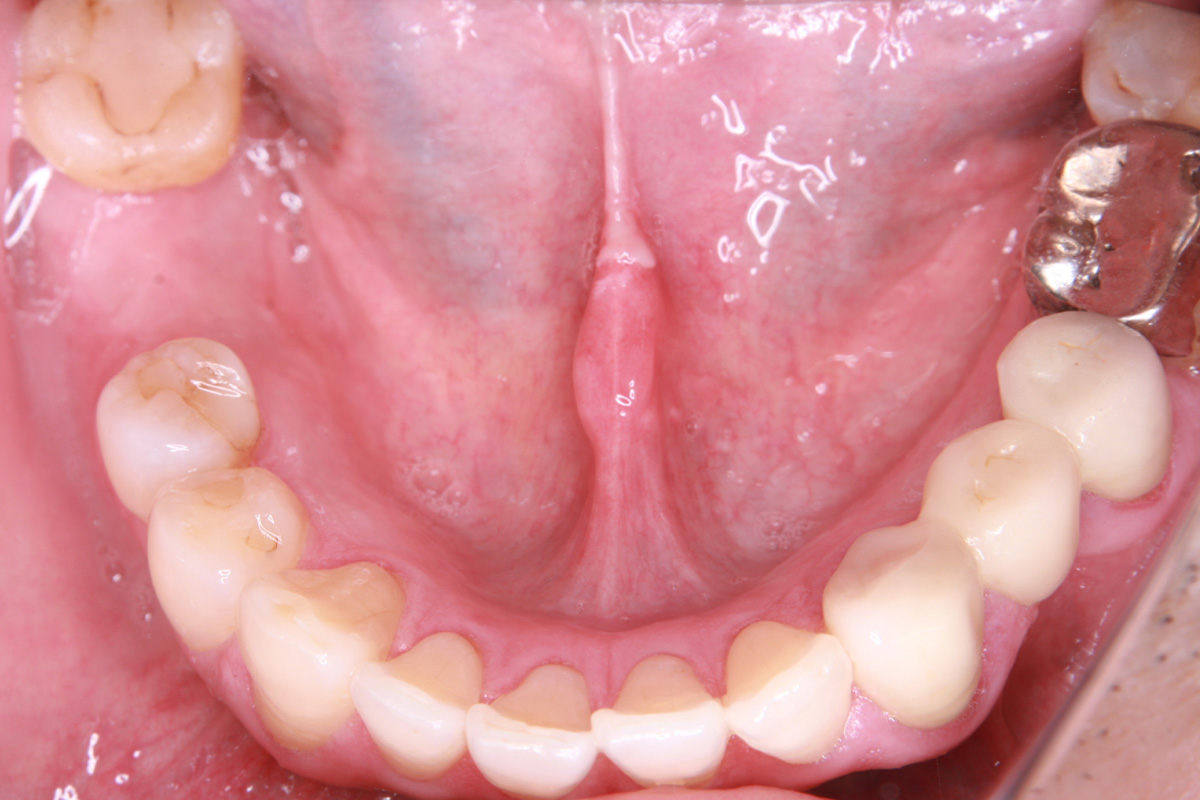

初診時

歯が割れていて、痛みがあり、抜歯となりました。

パノラマレントゲン写真 -

親抜歯後、歯ぐきは治癒しました。しかし、インプラント治療のためには骨が不足していました。